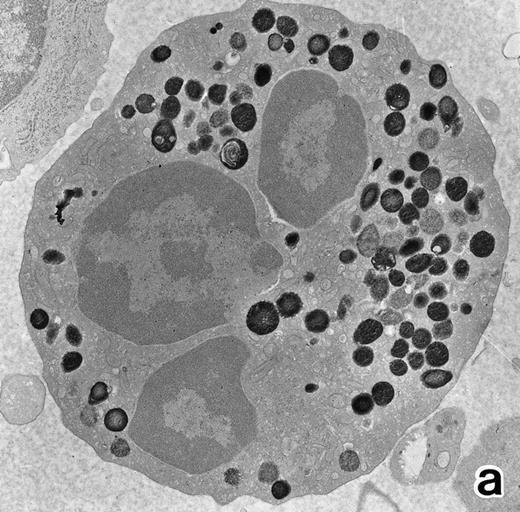

(a) A bone marrow leukemic cell in patient no. 1 at diagnosis containing abundant abnormally shaped primary granules, including Auer rods and Chediak-Higashi–type inclusions. Dilatation of rER is remarkable. (Original magnification × 10,800.) (b) Higher magnification of a cytoplasmic inclusion body of another cell in patient no. 1 that is membrane-bound and contains bundles of filamentous structures, similar to Auer rods. (Original magnification × 25,800.)

Electron microscopic observation.The leukemic cells of all three patients possessed abundant spherical (type I) primary granules containing electron-dense homogeneous material, with a peripheral halo in some granules and dilated rER (Fig 2a). Although type I primary granules predominated in all patients, small numbers of cytoplasmic granules containing crystalloid structures (type II primary granules) were also present in patient no. 1. Nuclear configurations were irregular, and the chromatin was only slightly condensed along the nuclear membrane. In addition to numerous Auer rods, the cells of patient no. 1 contained large cytoplasmic inclusion bodies also seen under the light microscope. These are the structures surrounded by a unit membrane and filled with parallel tubular material identical to that of Auer rods and belong to the psuedo–Chediak-Higashi (C-H) category of granules20,27 (Fig 2b). The cells of patient no. 3 contained smaller cytoplasmic granules than those of the other patients, and Auer rods were less frequently observed, a finding consistent with the M3 variant. Stellate rER complexes and fibrillar structures in the rER, both of which are thought to be structures specific to APL,28 were detected in this patient.